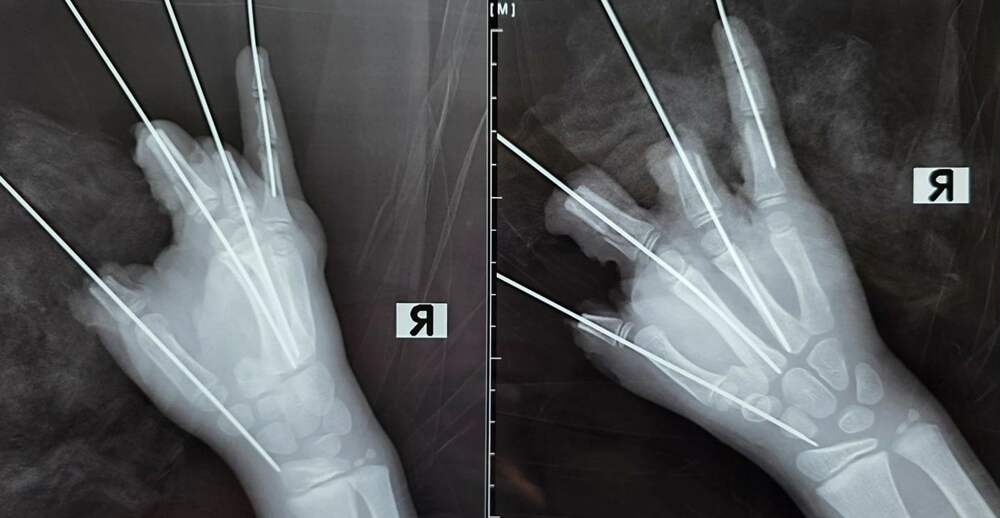

В Петербурге врачи ампутировали пальцы ребенку, в руках которого взорвалась петарда во время прогулки 11 февраля. Операция длилась пять часов. На данный момент мальчик находится в реанимации. Как рассказали в пресс-службе Педиатрического университета, врачи прооперировали ребенка, в руках... Далее